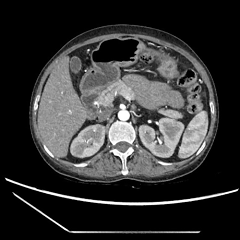

今年8月,李阿姨一家不远千里慕名来到瑞金医院嘉定院区消化道肿瘤多学科联合门诊就诊。就诊当天,来自胃肠外科、血管外科、放射科、病理科、肿瘤科、放疗科等多位专家仔细研读患者的病例及影像学资料,CT检查显示,李阿婆的肚子里竟有直径达30cm的巨大的脂肪肉瘤。肿瘤呈分叶状,填满了腹腔盆腔的间隙,挤压侵犯周围组织器官,病情异常凶险。

与多个腹腔重要血管关系紧密

血管外科冯家烜副主任认为:肿瘤血供丰富,且累及肠系膜上血管等多个重要血管,术中出血风险高,可预先DSA行肿瘤供血血管栓塞,减少术中出血;对于受侵血管,可切除后行血管重建。有了多学科保驾护航,瑞金医院副院长、嘉定院区普外科执行主任赵任教授表示:这个患者的手术虽然难度极高这个手术虽然难度极高,但是仍有根治性手术切除的机会!李阿姨一家看到希望的曙光,当即决定,为生命勇敢一搏!

术中发现,患者肿瘤不仅体积十分巨大,还侵犯包绕了肠系膜上静脉等多个腹腔重要血管!赵任教授精心剥除肿瘤,尽可能保留了小肠等器官血供,对于受侵严重的肠系膜上静脉,冯家烜主任为患者进行了血管修补重建。手术历经四个半小时,团队将重达4kg、直径近30厘米的肿瘤连同受侵部分小肠完整切除!